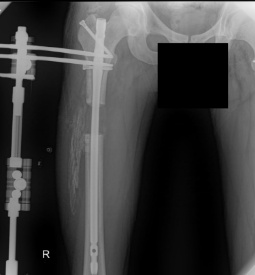

Success Story of Yusuf (8 cm -3.1 inch with lon method)

The process generally does not go as you planned, especially when there is pain, you can get upset I did not have nerve pain, but my lower legs were aching from time to time at 4.5 cm If we want the pain to decrease, the most important thing is to address them. We can reduce the pain by walking more and moving more. Pin site pain is very severe at 5.6 cm and can suddenly become unbearable and I applied to my doctor and limb lengthening istanbul patient responsible staff during these processes and they intervene in the wound, they widen the bottom of the needle due to tension, intervene in your wounds with a metal and clean the wound. Even the most durable and highest pain threshold patient cannot stop crying and screaming without a doubt. As a result, this The intervention is done for your own good and you feel better after 1-2 days. Especially the pain in the back pin affects your mobility and sleep a lot.

This surgery is really difficult and if you give up you will be defeated the most important thing is to be patient you should be above the budget you have set as an economy because there may be many additional expenses We stopped the extension yes but if you think your device will come out immediately you are wrong another psychological war is waiting period without extension. You have to wait for the bone to heal without turning for at least 1.5 months this period is much more difficult and does not pass than the period when doing extension but most of your pains will be relieved during this period If there are things you believe in during the process you want to see in the future and desire to live which is why I had this surgery you need to overcome all the obstacles you encounter there are many obstacles but breaking them all is in your hands and you have to suffer is in the nature of this job you heal by suffering actually you have two options either you will continue on your way or you will continue on your way even if there are negative things at the beginning of the process you actually live this process with your mentality completely independent of your body. When I had pain I would talk to my body come on man let there be more pain more pain will not make me give up It makes you stronger and after a while your brain wins over your body :)